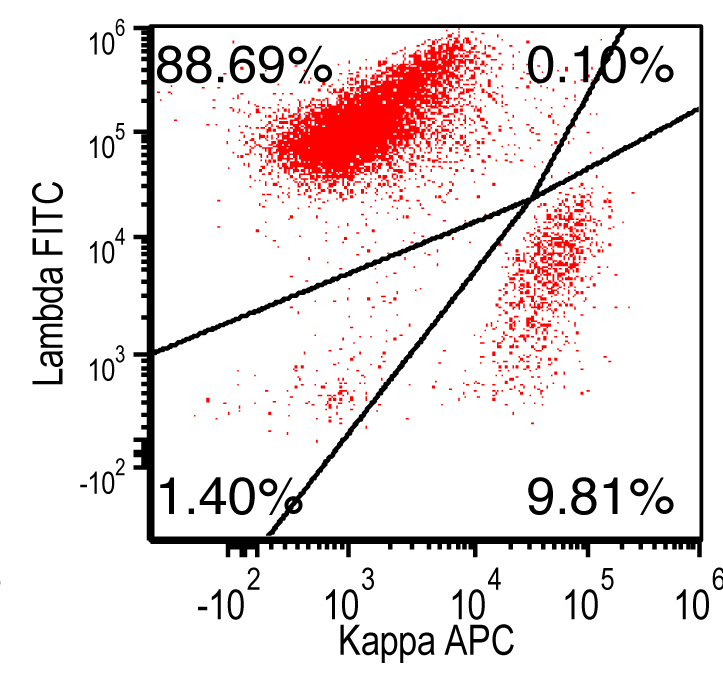

- Flow cytometry: monoclonal B cells with typical immunophenotype and monoclonal plasma cells

- Immunophenotype of LPL cells: IgM+, CD19+, CD20+, CD22+, CD25+, CD10-, CD23-, CD103-, variable CD138

- Immunophenotype

- Positive: IgM, CD19, CD20, CD22, CD79a, CD25 and CD38 frequent expression

- Negative: CD5, CD10, CD103, CD23; however, CD23 expression is not uncommon in some cases

Flow cytometry description

Flow cytometry images

Contributed by Ling Zhang, M.D. and Caroline An, M.D.

- Immunohistochemical study: Immunohistochemical stains and in situ hybridization stains are performed on the core biopsy with adequate controls. CD20 and PAX5 highlight a diffuse infiltration of neoplastic B cells, occupying 80% of total cellularity. CD3 highlights scattered interstitial T lymphocytes, ranging from 2% to 5%. CD138 highlights scattered plasma cells, focally forming small clusters, accounting for approximately 5% of the total cells. By in situ hybridization (ISH), the plasma cells are positive for kappa light chain and negative for lambda light chain.